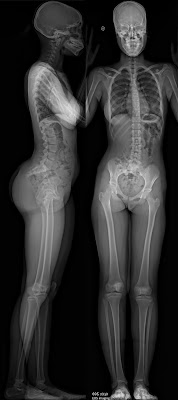

Специализированные клиники, в которых проходят лечение пациенты с деформациями позвоночника, используют метод рентгенографии. Тело человека снимают в положении стоя на длинную пленку без разрывов (панорамный снимок).

Так как в клинической практике оценки деформаций позвоночника наиболее удобен метод рентгенографии, ученые выяснили взаимоотношения между изменением центра тяжести и графическое отображение тела человека. Как раз для этого и нужны снимки всего позвоночника в положении стоя. Было установлено, что гравитационная линия всегда параллельна отвесу из седьмого шейного позвонка.

Так как наиболее выгодная позиция для оси позвоночника — положение рядом с гравитационной линией, то у сбалансированного позвоночника отвес из седьмого шейного позвонка на рентгенограмме в положении стоя проходит рядом с крестцом (в передне-задней и боковой проекциях) и через головки бедренных костей. Допустимым отклонением от крестца считается 4 см.

В большинстве случаев с возрастом уменьшается величина поясничного лордоза. Происходит это из-за дегенеративных изменениях в межпозвоночных дисках (они теряют воду и становятся более плоскими), а так же при изменении формы тел позвонков на фоне остеопороза. Иногда такие изменения сопровождаются сколиотической деформацией в поясничном отделе. Этот сколиоз отличается от подросткового и не является его следствием. Посмотрите как со временем у пациента со временем уменьшался лордоз.